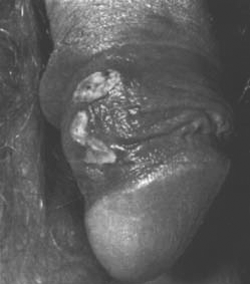

Sifilide I stadio (pene)

Sifilide II stadio (torace)

Evoluzione:

Sifilide III stadio (piedi)